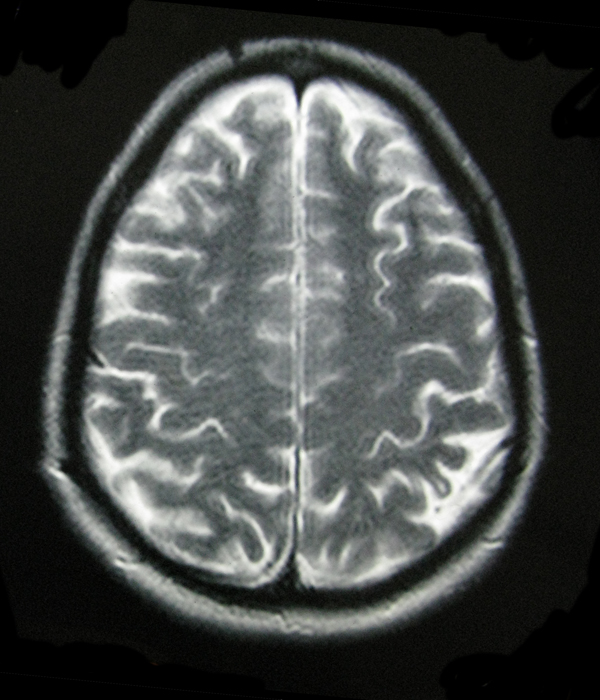

- My Brain in 2009